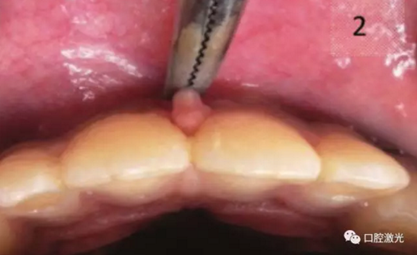

術(shù)中

拉緊嘴唇,切到接近骨膜暴露

手用器械暴露骨膜,防止纖維再附著

去除所有阻擋肌纖維